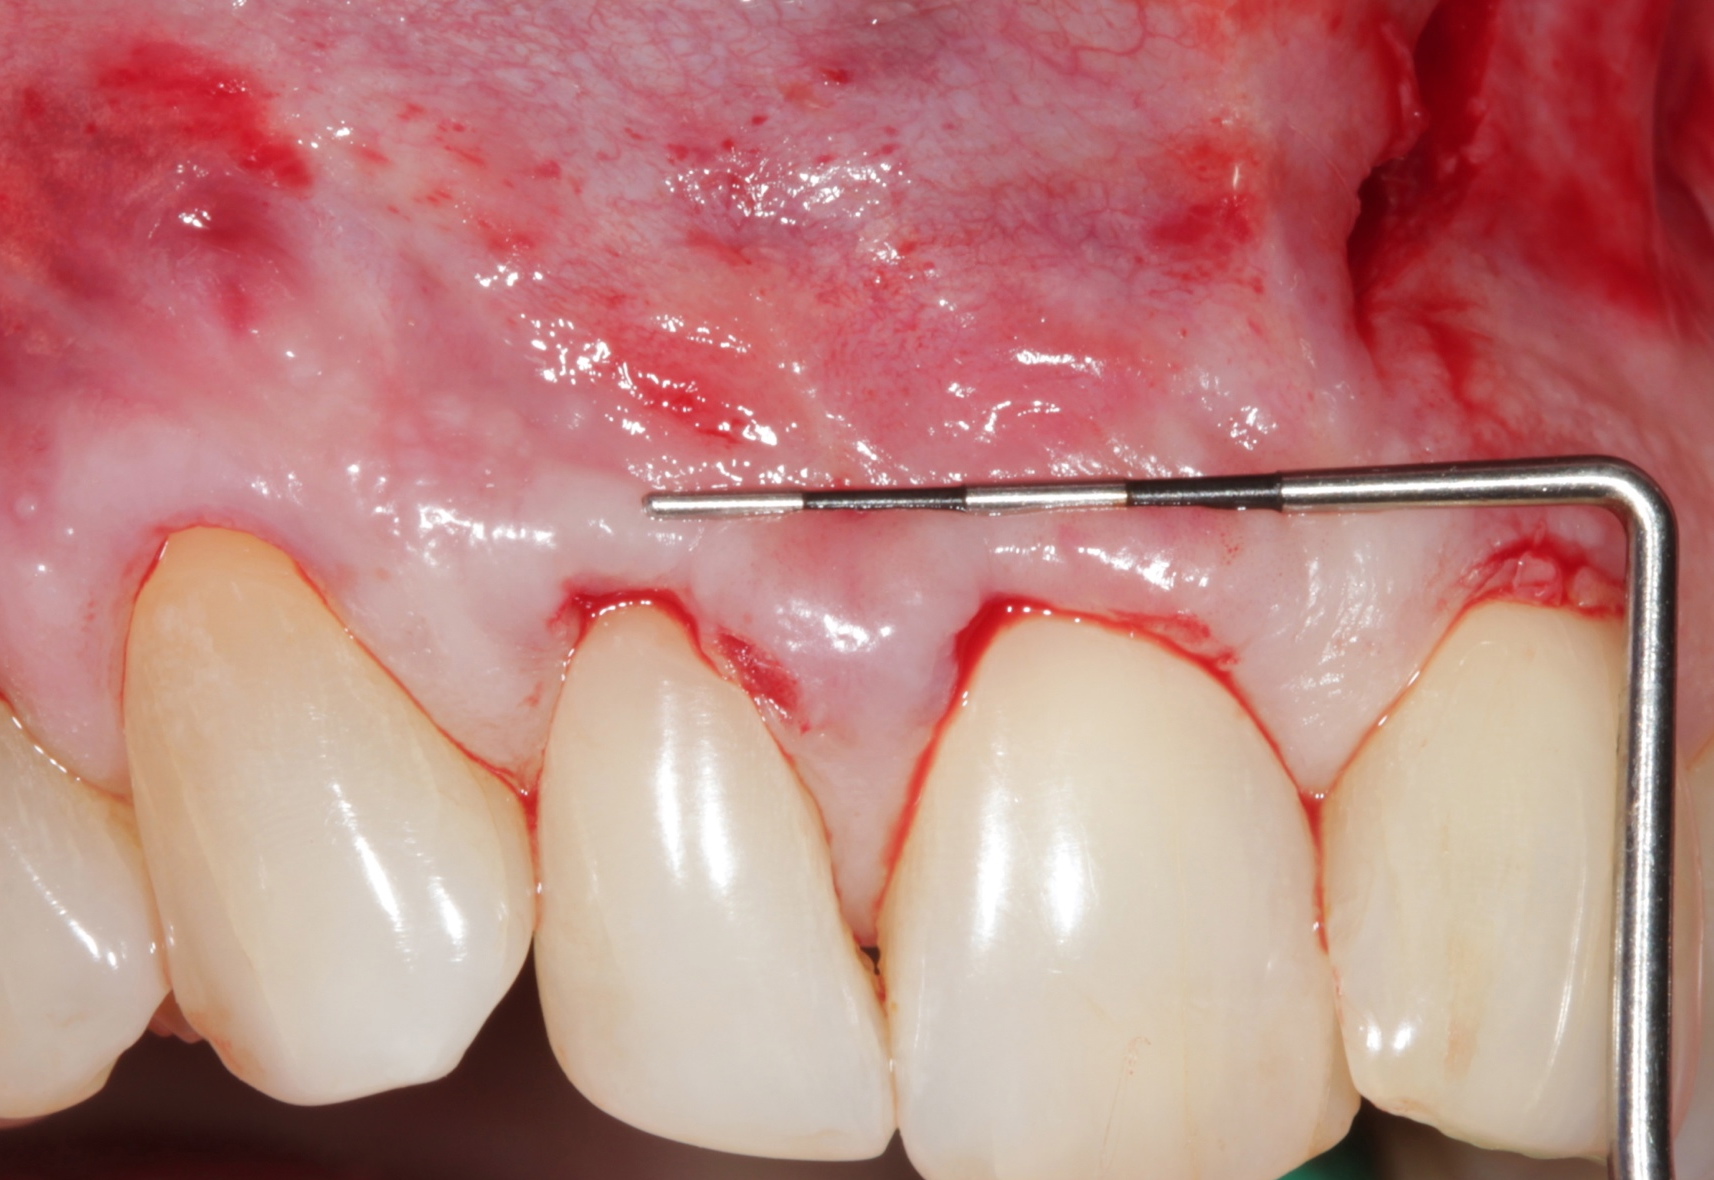

Volume Packing

For clinical significance, clinicians should use a minimum of 3 to 4 membranes per pair of teeth. A “backpacking concept” from the distal to mesial aspects will provide a homogenous density of APRF membrane volume (Figure 7).

Fig 7. APRF membrane placement. A “distal-mesial backpack” technique ensures a dense and complete packing of the APRF membranes in the pouch created. Three to 4 membranes are recommended per pair of teeth treated.

Figure 7